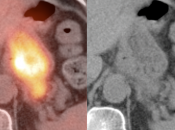

False Positives:

• Normal Physiologic Uptake: This is, far and away, the most common etiology of diffuse or segmental gastric uptake, even if very intense.

• Inflammation/Gastritis: Can be diffuse or focal.

• Gastric Ulcer: May present as a small focus of intense uptake. Will require evaluation with upper endoscopy.

• Hiatal Hernia: Increased metabolic activity is frequently encountered within a hiatal hernia. Such uptake is nearly always physiologic or inflammatory. Malignancy, however, sometimes cannot be excluded and upper endoscopy may be required.